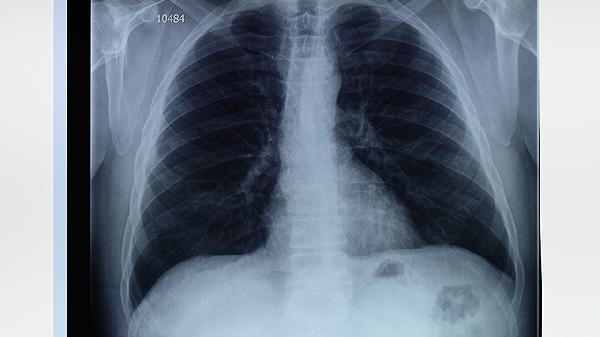

肺气肿与肺大泡患者需严格戒烟并避免粉尘接触,饮食宜选择高蛋白、高维生素食物如鱼类、西兰花以增强免疫力。规律进行太极拳、散步等低强度运动可改善心肺耐力,但应避免屏气动作。冬季注意保暖防感冒,监测血氧饱和度低于90%时需及时就医。每年至少进行一次肺功能检查和胸部影像学评估,合并糖尿病或高血压者需同步控制基础疾病。